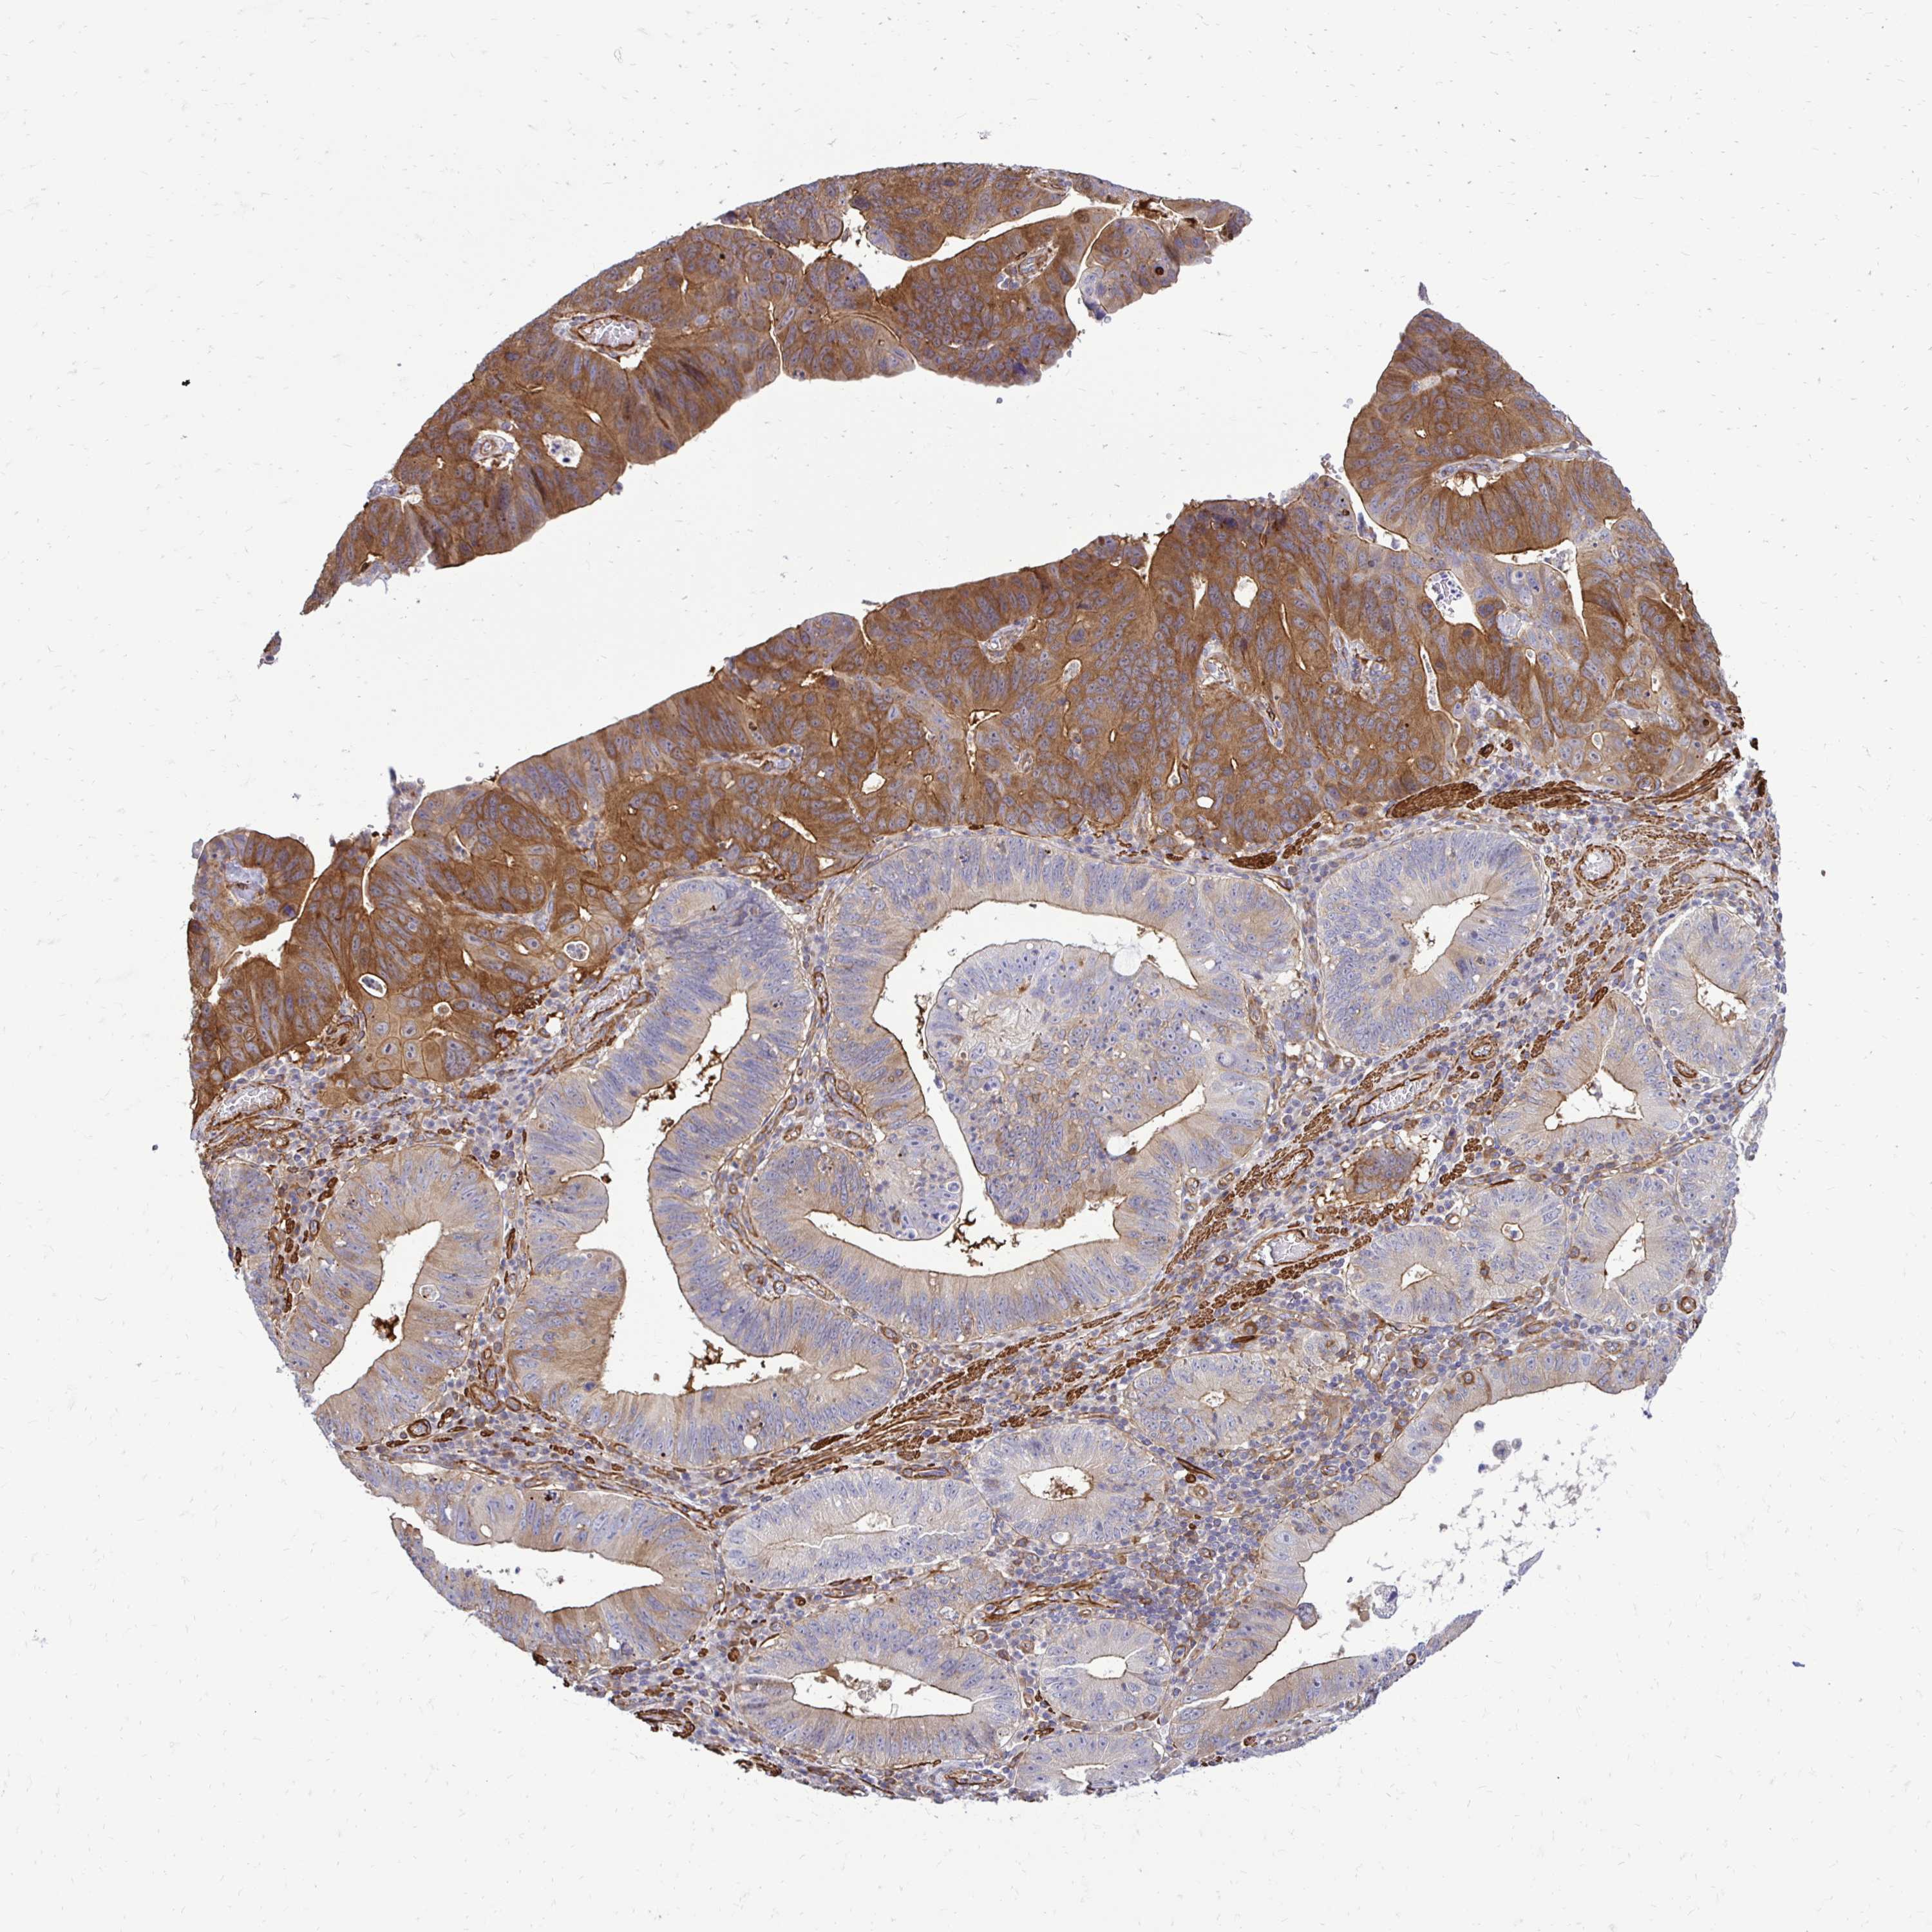

STOMACH CANCER - Protein expressioni

A mouse-over function shows sample information and annotation data. Click on an image to view it in a full screen mode. Samples can be filtered based on level of antibody staining by selecting one or several of the following categories: high, medium, low and not detected. The assay and annotation is described here.

Note that samples used for immunohistochemistry by the Human Protein Atlas do not correspond to samples in the TCGA dataset.

Antibody stainingi

Antibody staining in the annotated cell types in the current human tissue is reported as not detected, low, medium, or high, based on conventional immunohistochemistry profiling in selected tissues. This score is based on the combination of the staining intensity and fraction of stained cells.

Each image is clickable and will lead to virtual microscopy that enables deeper exploration of all samples and also displays staining intensity scores, fraction scores and subcellular localization as well as patient and tissue information for each sample.

Antibody HPA051322

Antibody CAB017111

Staining

High

Medium

Low

Not detected

Intensity

Strong

Moderate

Weak

Negative

Quantity

>75%

75%-25%

<25%

None

Location

Nuclear

Cytoplasmic/membranous

Cytoplasmic/membranous,nuclear

Adenocarcinoma, NOS

Adenocarcinoma, High grade